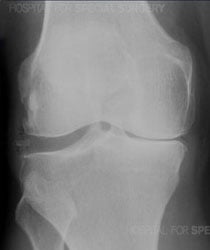

X-ray of an arthritic knee

Knee arthritis literally means "inflammation of the knee joint," although inflammation is not always present when there is arthritis. On an X-ray of a knee with arthritis, the space between the upper and lower bones is often reduced or, in some places, even absent due to loss of cartilage, the shiny material which covers the ends of the bones.

X-rays are very helpful in diagnosing advanced knee osteoarthritis because the joint will have specific characteristics, including:

- Bones that are closer to each other than they should be: As cartilage wears away, the joint space between them often narrows.

- Cysts: As the body responds to cartilage destruction and attempts to stabilize the joint, cysts or fluid-filled cavities can form in the bone.

- Increased bone density or uneven joints: When bones are no longer cushioned by cartilage, they can rub against one another, creating friction. The body responds by producing more bone tissue, which increases bone density. Increased bone creates uneven joint surfaces and bone spurs at the joint.